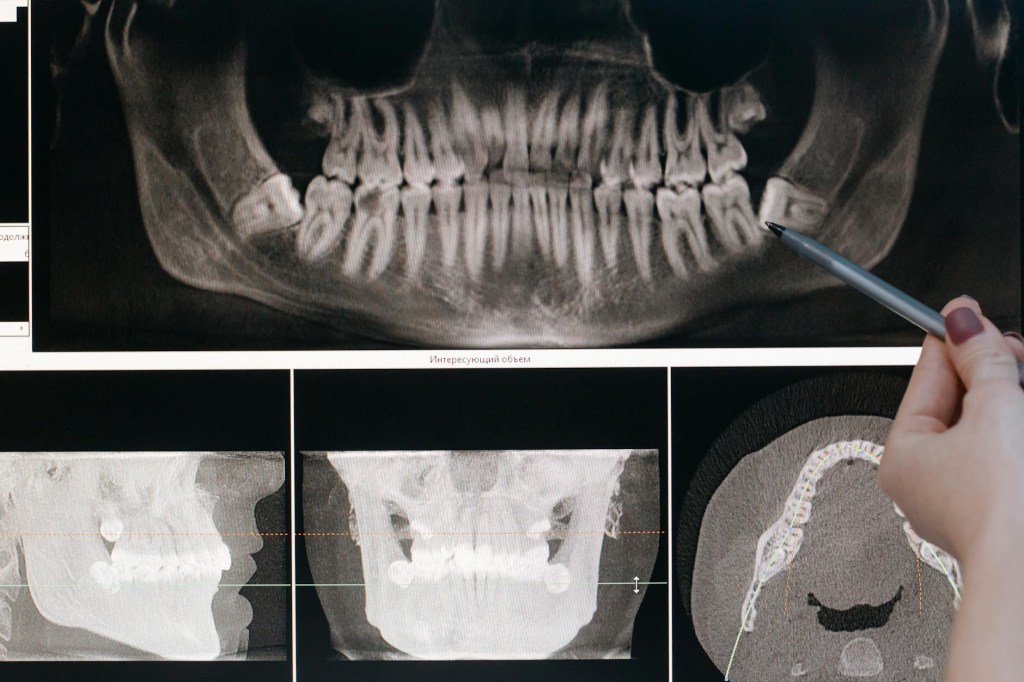

すでに右側は10年以上前に上下とも抜いた。特に下の親知らずは、見事に真横に生えていて、歯茎の中で完全に寝そべって、所狭しと横の歯を押しているような状態だ。そのため、歯医者さんがハンマーのような器具で砕きながら取り出すという、なかなかワイルドな手術になった。あの時の音と衝撃は、麻酔をしていたとはいえ、今思い出しても背筋がゾワッとする。

そして今、残っている親知らず達。この上の奴が、欠けてしまっているのだ。が、痛みはまったくない。先日の全身麻酔時に術前処置で歯科で削ってくれた。奥歯が欠けるのはご想像通りだ。たぶん。彼らをこのまま放置すれば確実にトラブルになる可能性はある。虫歯、炎症、噛み合わせの悪化…未来の自分に負担を押しつけるだけだ。が、いざ抜くとなったら…とはいえ、いざ「抜きましょう」と言われると、痛くもない歯をわざわざ抜くという行為は、どうしても気持ちが追いつかない。頭では分かっている。今のうちに抜いた方がいい、後で痛むよりマシ、治療は早い方がいい、でも、心は別の声を出している。本当に今なのか、またあの時の、、、更に上が、痛くないのに抜くなんて…と、この葛藤こそが、親知らずの怖さなんだと思う。